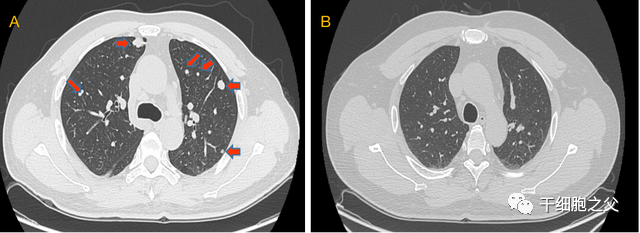

01.肝癌术后复发伴肺部转移,细胞免疫疗法成功消除肿瘤